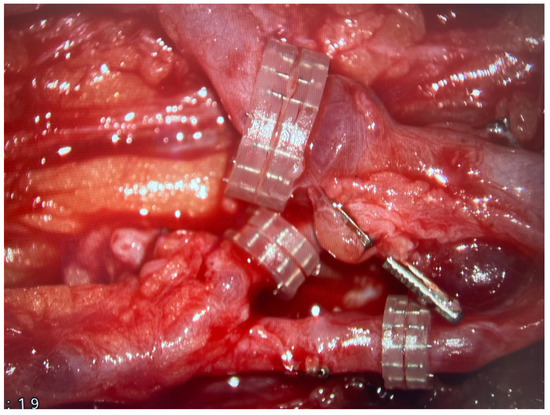

All flaps were harvested, including a skin paddle, as a monitor of transferred tissues’ viability and to avoid the necessity for performing angiographic studies to assess the blood perfusion within the fibula (Figure 2).

All flaps were harvested, including a skin paddle, as a monitor of the transferred tissues’ viability and to avoid the necessity for performing angiographic studies to assess the blood perfusion within the “hidden” fibula.

It is of paramount importance, as in the case of inadequate blood supply to the transferred bone, the osseointegration of the flap with the adjacent bone stumps is considerably impaired and, in many cases, even impossible to achieve. Moreover, harvesting the skin island as a component of the FFF, apart from making tissue dissection more technically demanding and the need to identify skin perforators, does not carry any additional burden for the patient. Simultaneously, it allows for continuous monitoring of the buried bone in a safe and objective way without the need for imaging tests such as CT angiographs, which expose patients to radiation and nephrotoxicity related to the injected contrast [27,28,29]. In all cases, the donor sites were closed tension-free primarily, without the need for skin grafting (Figure 6). The skin island covering the vascularized bone graft additionally reduced the skin tension within the treated limb, which could have contributed to such a rare wound healing disorder in the analyzed group of patients (5%). Considering the above, it is difficult to find a reasonable explanation for not routinely taking into account the skin island as an external “monitor” during FFF harvest (Figure 8).

What should be emphasized, as excessive compression of the flap pedicle by surrounding tissues is a well-known risk factor for flap venous insufficiency, ref. [33] harvesting the above-mentioned skin paddle of the fibula free flap, which after inset of the flap significantly reduces the tension within the skin of the forearm should be considered as a protective factor for flap’s blood outflow.

Figure 8. An intraoperative photograph of a skin island’s inset within the treated upper limb—a healthy skin paddle without signs of vascular congestion. Attention is drawn to the tension-free closure of the skin layers within the forearm.